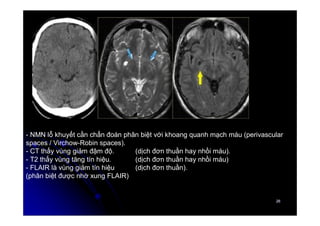

- NMN lỗ khuyết cần chẩn đoán phân biệt với khoang quanh mạch máu (perivascular

spaces / Virchow-Robin spaces).

- CT thấy vùng giảm đậm độ. (dịch đơn thuần hay nhồi máu).

- T2 thấy vùng tăng tín hiệu. (dịch đơn thuần hay nhồi máu)

- FLAIR là vùng giảm tín hiệu (dịch đơn thuần).

(phân biệt được nhờ xung FLAIR)